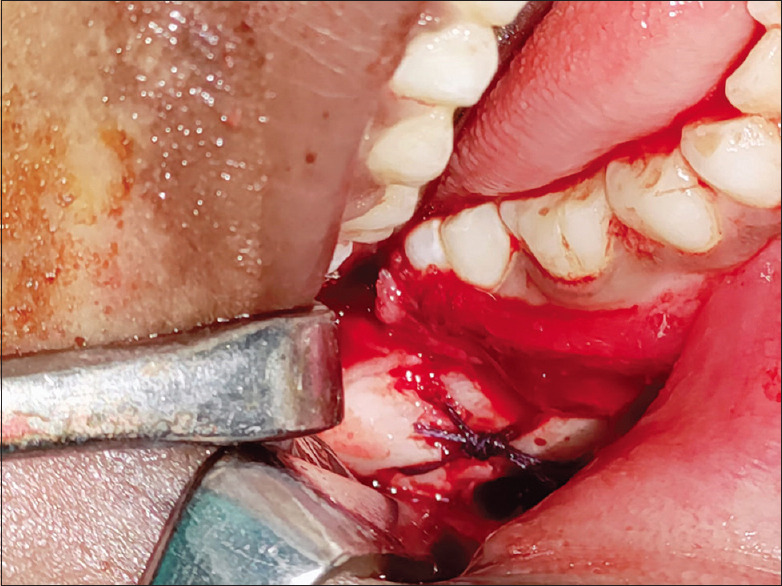

Technique: After raising a full-thickness mucoperiosteal flap, the fracture segments are identified and reduced. 1.6mm drill bit is used to make holes through the buccal cortex on either side of the fractured segment in an anteroposterior direction. The patency of holes is checked by passing a long 26-gauge wire. The proximal end of the wire is bent into a loop, a 2-0 resorbable polyglactin suture (vicryl) is passed through this loop and the loop is pressed in place to lock the suture. The wire with the attached suture is pulled through the distal end. Once the suture is secure in place, the 26G wire is cut, and the two ends of sutures are knotted and stabilised. The mucoperiosteal flap is then closed.